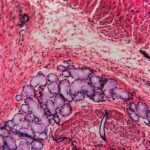

Hemangiosarcoma (HSA) in dogs is a malignant, aggressive cancer in dogs that starts within the cells lining blood vessels (endothelial cells). According to the Flint Animal Cancer Center, hemangiosarcoma in dogs is a fairly common cancer, accounting for about 5% of total cancer cases.

As a cancer of the cells lining blood vessels, hemangiosarcoma in dogs can occur anywhere in the body. However, there are several sites that are most commonly affected by this cancer: skin, spleen, heart, and liver. There are two main hemangiosarcoma tumor types:

• Cutaneous Hemangiosarcoma in Dogs. Hemangiosarcoma of the skin surface is a common tumor of the endothelial cells lining the skin blood vessels. This form of hemangiosarcoma is locally aggressive and has a high rate of spreading to other organs.